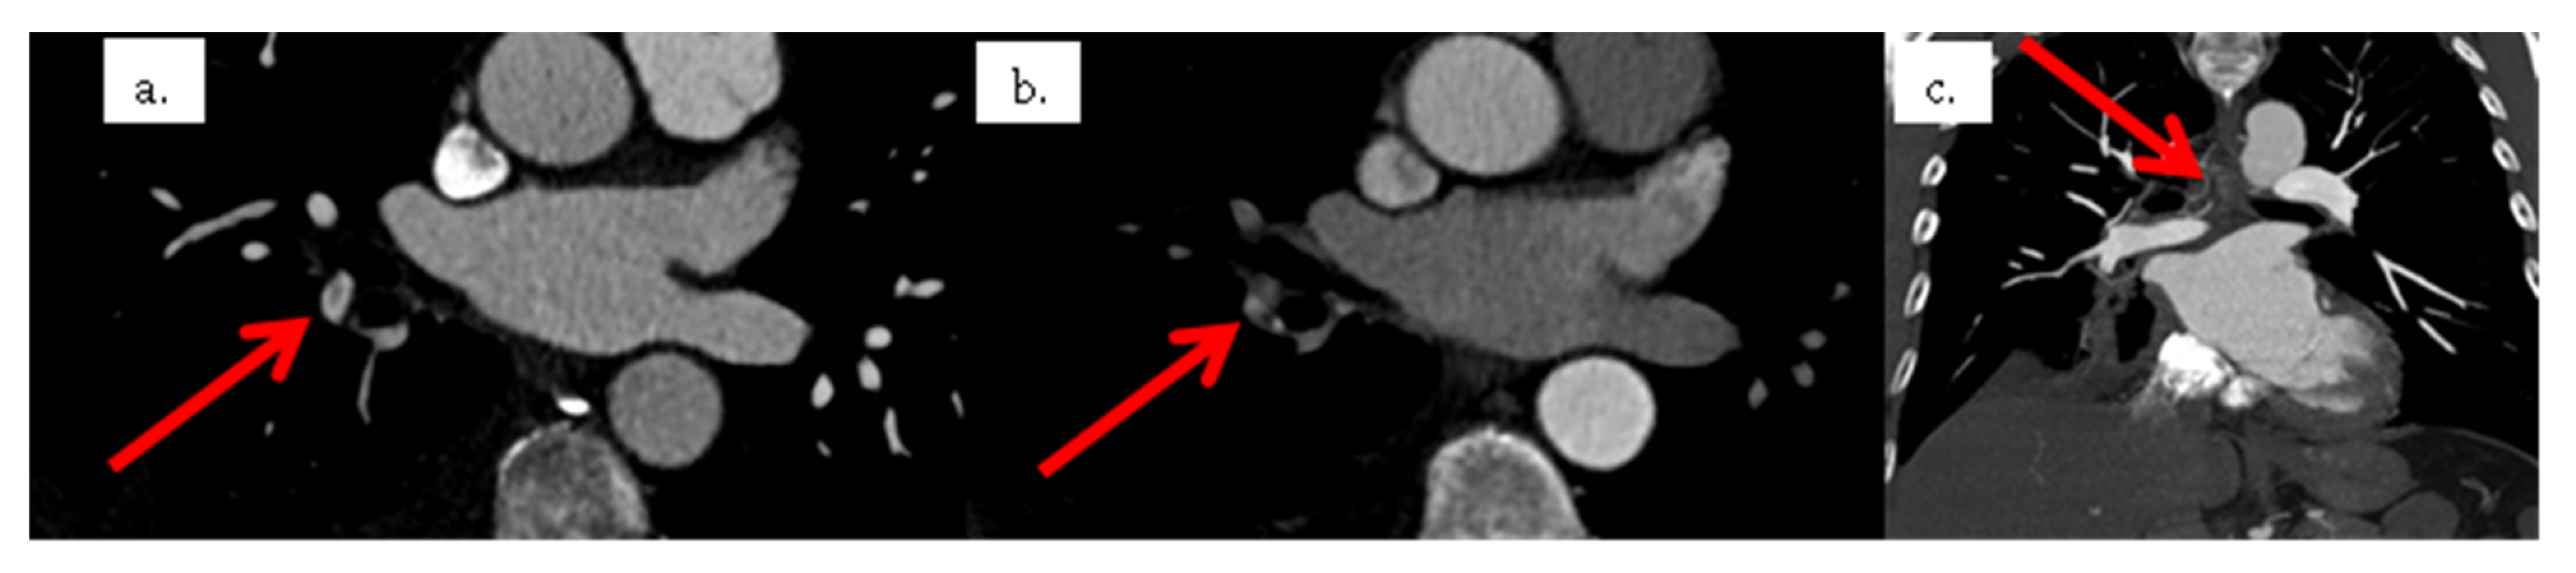

2. Case Presentation